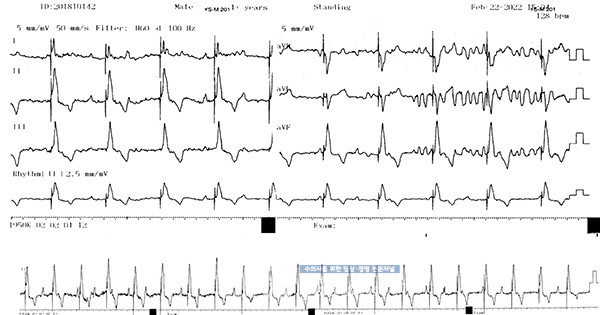

VVIR에서 속도를 90~150bpm에서 100~150ppm으로 조정하였습니다.

수술 후 10일, AV block이 관찰되지 않습니다.